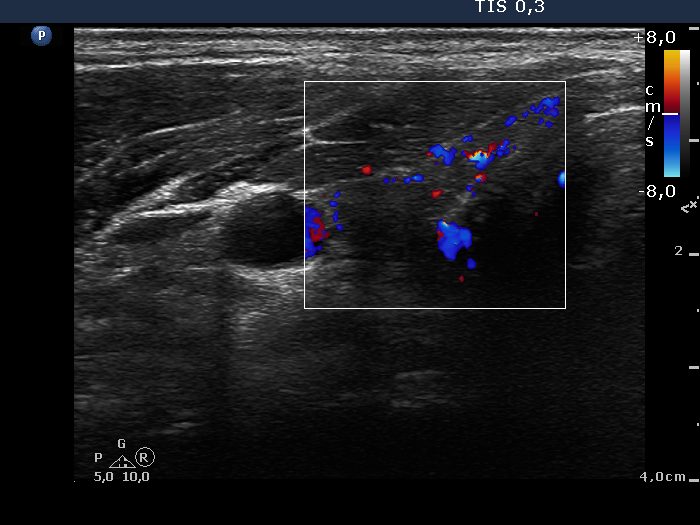

Ultrasonography: Both lobes presented hypoechogenic ill-defined areas. The echogenicity index was 80% in the right lobe while 20% in the left thyroid. The vascularization was significantly decreased.

Ultrasonography: The size of the thyroid decreased dramatically and became atrophic. The right lobe still presented a small deeply hypoechogenic area. In contrast with the first examination, the basic echo structure of the left lobe was not normal but moderately hypoechogenic. The vascularization was decreased and average, right and left lobe, respectively.

Ultrasonography: The pattern remained basically the same.